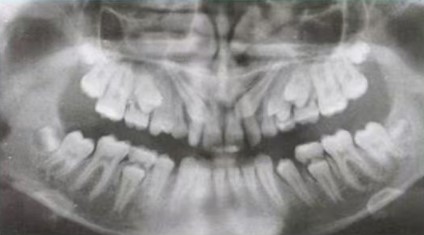

医生通常会通过X光片来观察。当发现恒牙的牙根已经发育到3/4长度时,就表示它已经蓄势待发,准备萌出了,此时,对应的乳牙就应进入生理性的松动、脱落阶段。

1.乳牙过于稳固:X光片显示恒牙牙根已经发育充分,但乳牙丝毫没有松动迹象。

所以,家长们,请不要过度焦虑,更不要自己动手摇晃或强行拔除孩子的乳牙。建议在孩子换牙期间定期进行口腔检查。医生可以通过临床检查和X光片,精准评估恒牙的位置和发育阶段,从而在最佳时期(通常在恒牙根形成3/4左右)做出专业判断,决定是否需要干预,以确保恒牙能够顺利、整齐地萌出。